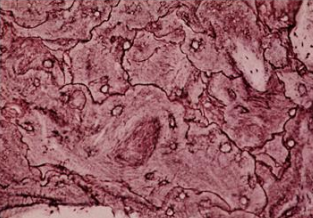

How do you know this patient does not have bone loss due to osteoporosis?

Giant osteoclasts are taking bites out of the bone and osteoblasts are working to build bone. The highly cellular surface indicates tremendous bone turnover typical of Paget’s disease.

How does hyperparathyroidism differ from Paget’s disease?

Lots of osteoclast activity and little osteoblast activity. You will also have high blood Ca levels and PTH levels not evident in Paget’s disease.